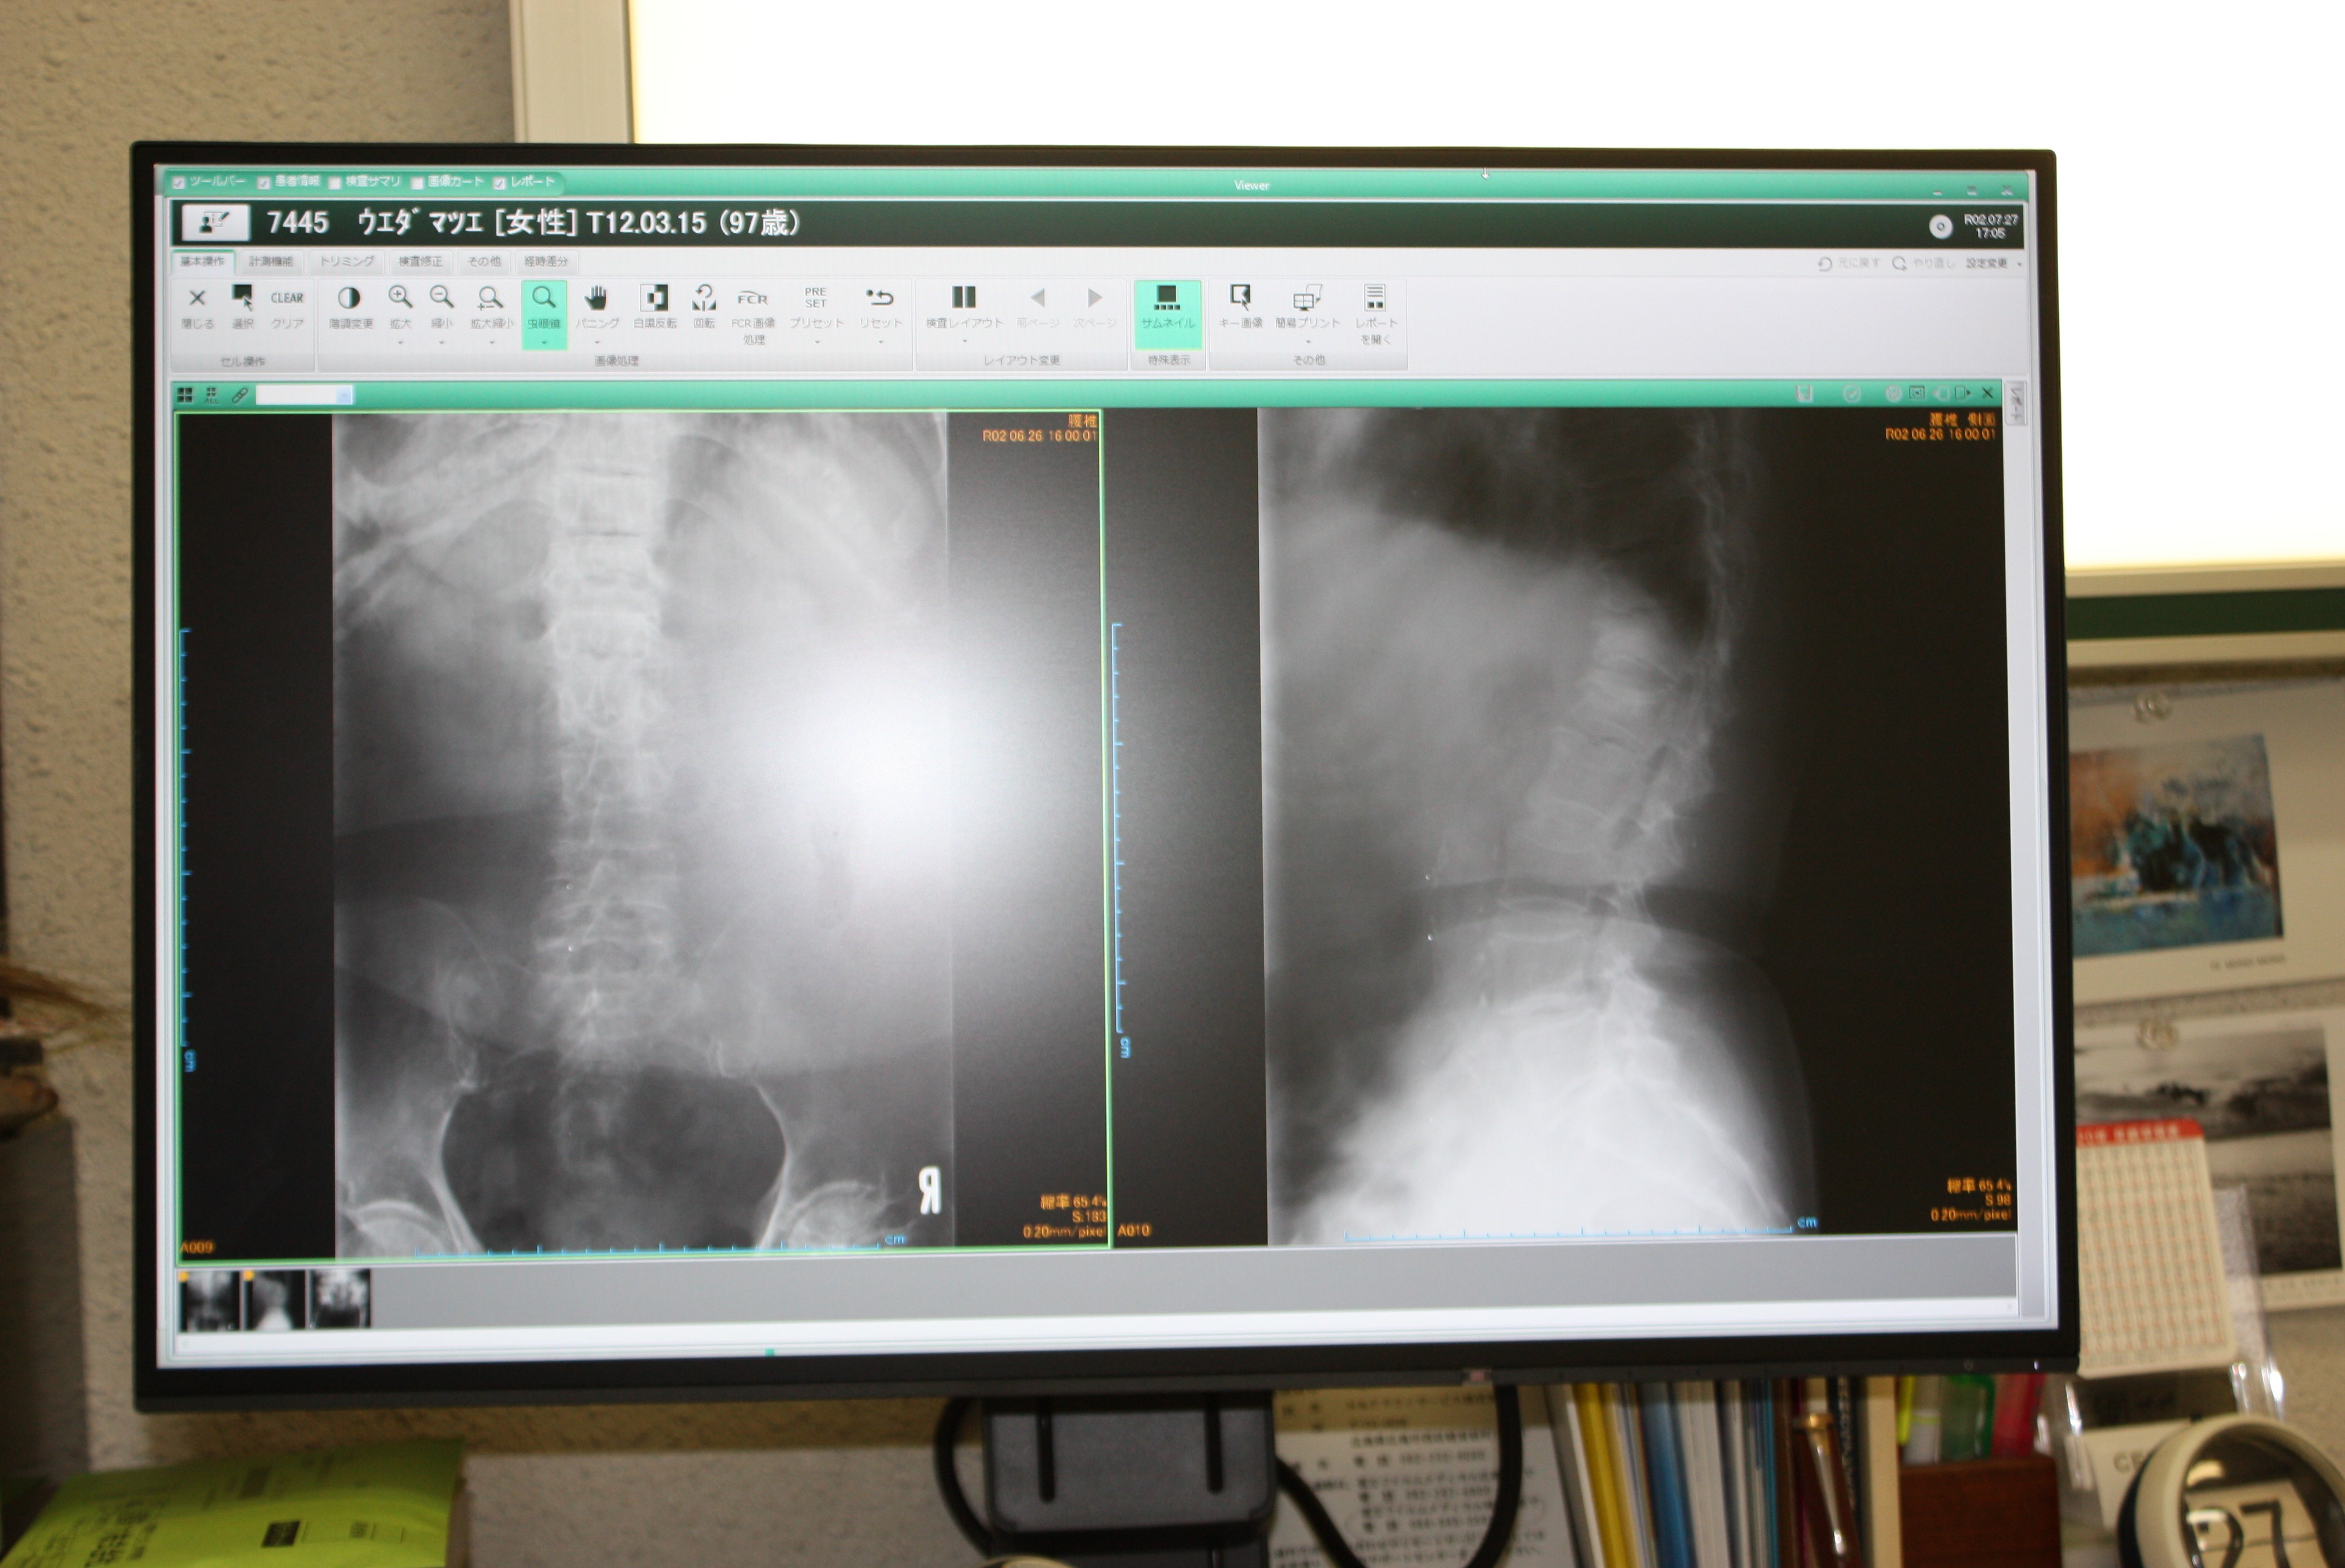

さすがに医療器械の進歩は著しく、全てがとてもコンパクトになりましたが、何よりもびっくりしたのは画像がとても鮮明になったことです。

いままで老眼で一生懸命に読影していたのがうそのように楽になりました。